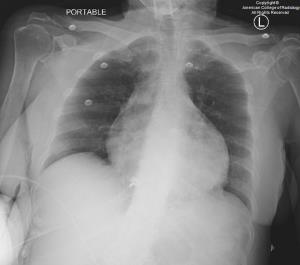

Read the Bulletin » Read the JACRTest your clinical knowledge with the daily Case in Point program, which gives you the opportunity each weekday to work through a subspecialty case.